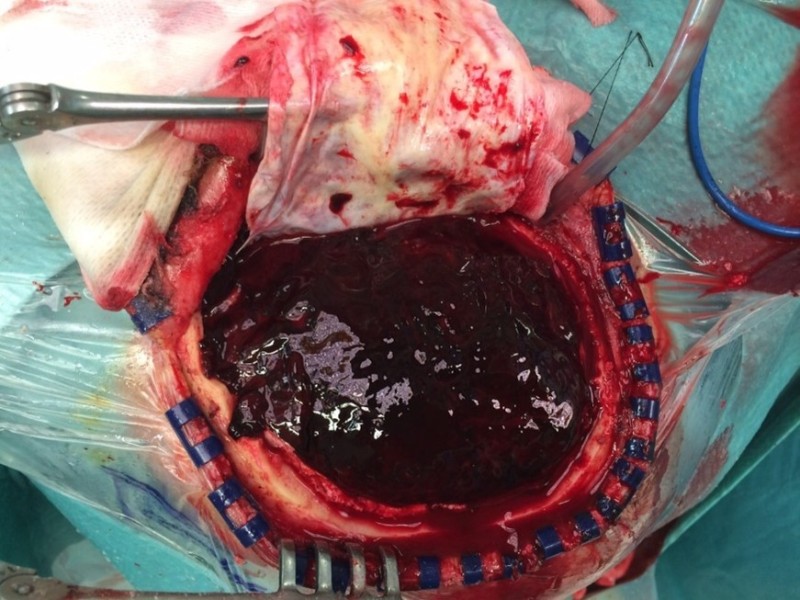

Imagen 47. Hematoma subdural.

Imagen 48. Hematoma subdural drenado.